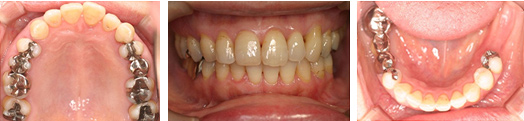

50代 女性

主訴 歯がグラグラしてかめない

治療内容 歯周治療 再生療法 歯肉移植

インプラント治療 サイナスリフト 垂直的骨造成

治療前